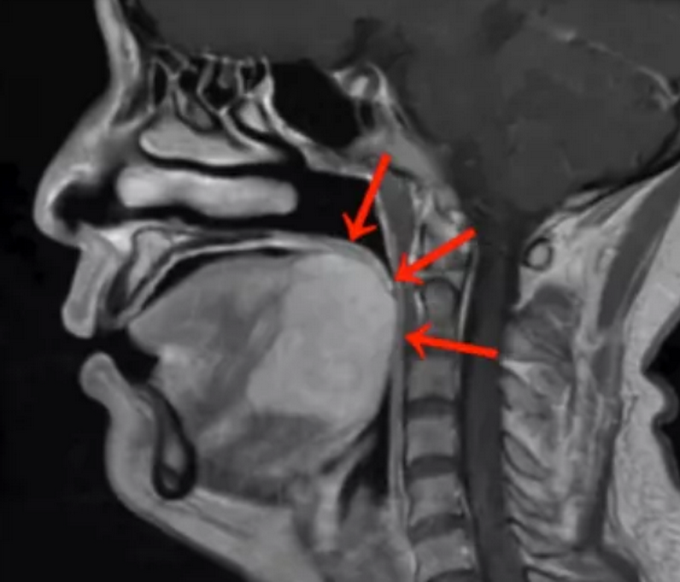

8月22日据媒体报道,刘女士到社区做核酸检测时,意外发现舌根下竟藏有一个巨大肿块。刘女士便于近日来到广州中山大学肿瘤防治中心求医,经诊断为舌根癌。

“刘女士得的这种舌根腺样囊性癌较罕见,对放化疗不敏感,手术是刘女士的最佳治疗选择。”

面对刘女士舌根部肿物体积巨大的情况,宋明陷入了两难:按传统的手术治疗方式,刘女士是需要接受开放性手术的,但这种术式需要将下唇及下颌骨裂开才能暴露并切除舌根肿瘤。

医者父母心,面对才40来岁的刘女士,宋明建议她采用经口机器人手术。手术仅用时90分钟,出血量不足50毫升,成功将舌根肿瘤完整切除,并保证足够的安全边界,而且无需进行气管切开术。

舌根癌是长在舌根部的恶性肿瘤,是上皮来源的恶性肿瘤,所以称为癌。可以分为几大类,常见的是鳞状上皮癌,还可以有腺癌、淋巴上皮癌等。因为长在舌根部也就是长在舌后1/3,在口腔当中不可以直接看到,所以很隐蔽,早期不容易被发现。而舌根癌早期又没有什么症状,一旦发现往往是中期或者晚期。因为早期没有症状,所以长的比较快,慢慢会出现疼痛,只有出现疼痛以后病人才能到医院就诊。到医院就诊可以拍摄CT,可以看到舌根部长了一个肿物,一般都是菜花样,如果比较大可能会影响吞咽或者咽部有异物感。如果得了舌根癌需要尽早进行手术治疗,根据病理情况配合其它治疗。